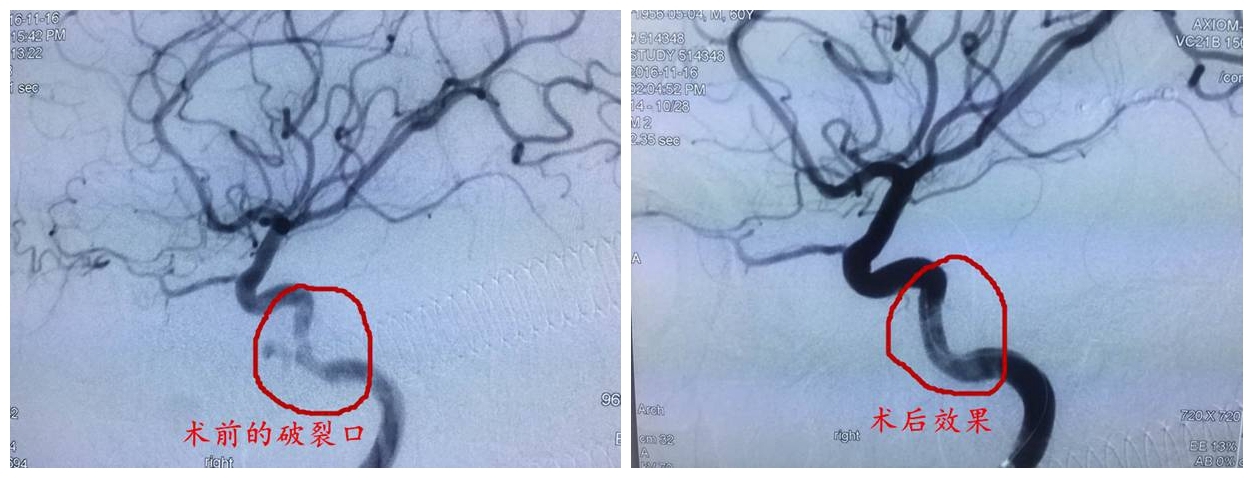

神經(jīng)外科李雪松主任對(duì)該病例高度重視,邀請(qǐng)了介入科、DSA導(dǎo)管室、腫瘤科、耳鼻喉科、麻醉科、ICU進(jìn)行多學(xué)科聯(lián)合診療,為患者制定最優(yōu)化的治療方案。11月16日,李雪松主任在饒強(qiáng)醫(yī)生的配合下,對(duì)患者施行了全腦血管造影術(shù),術(shù)中造影果然發(fā)現(xiàn)了右側(cè)頸內(nèi)動(dòng)脈海綿竇段假性動(dòng)脈瘤。經(jīng)與家屬共同決策,李主任采取了覆膜支架介入手術(shù),術(shù)程順利,術(shù)后患者恢復(fù)良好。